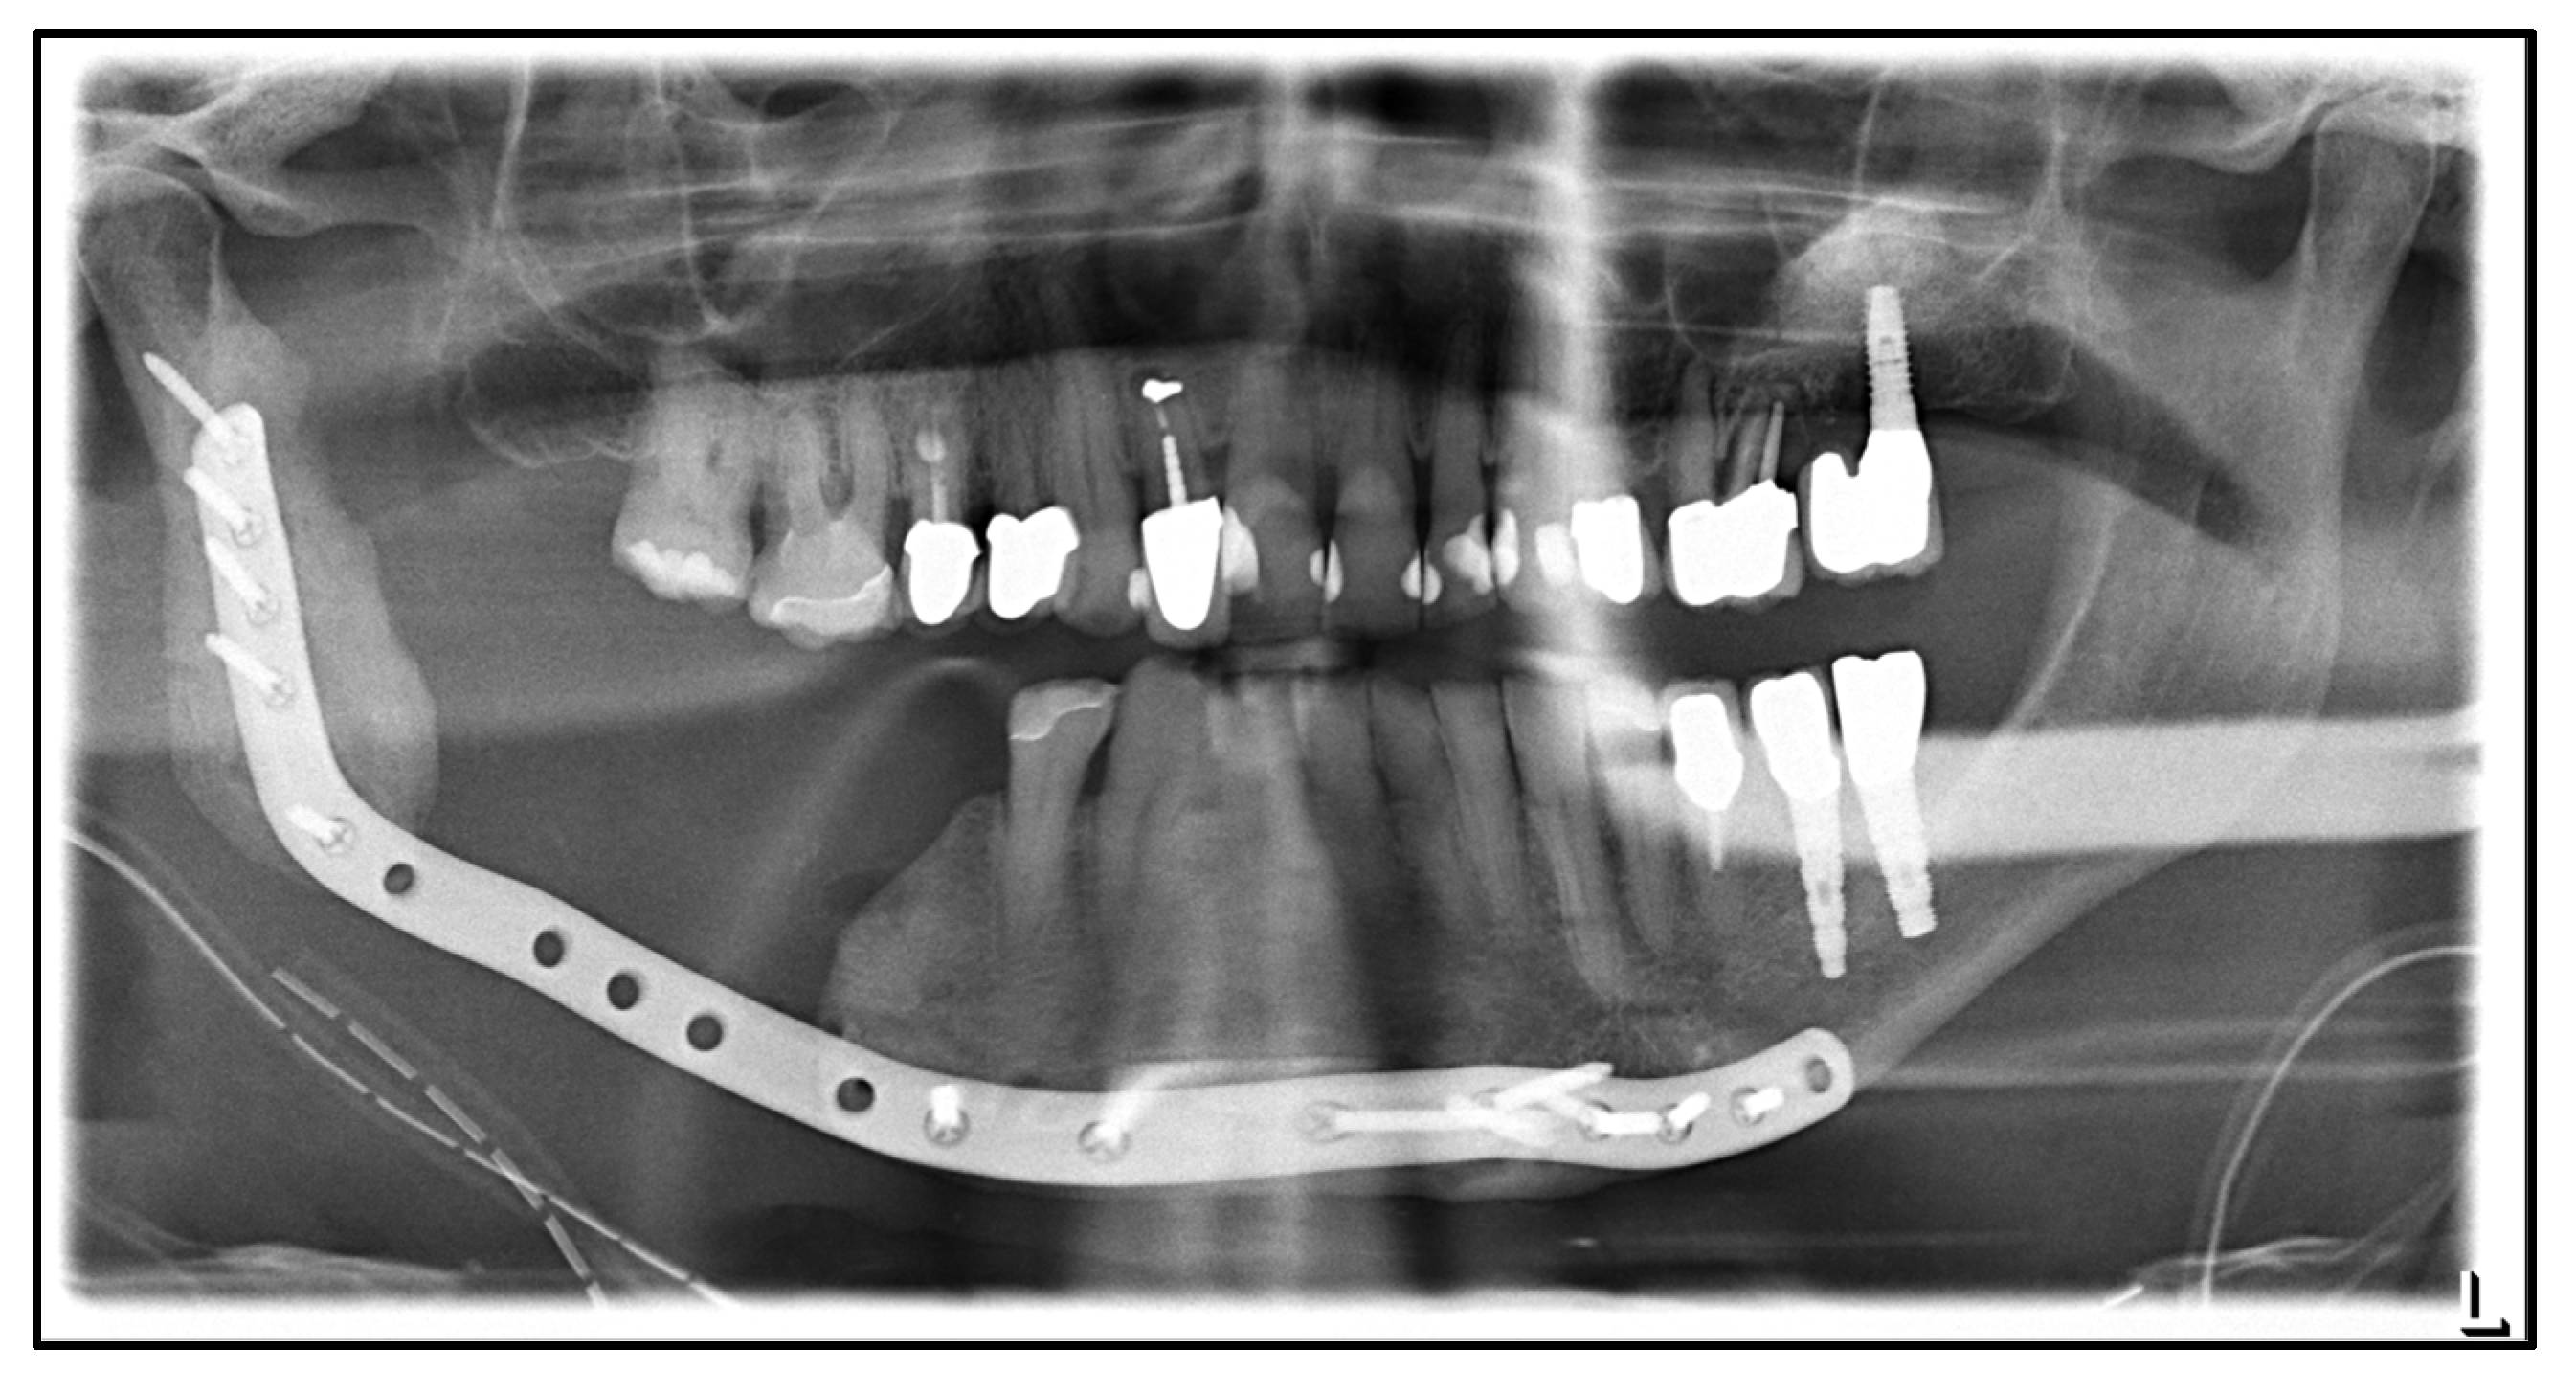

| July 2014: | Diagnosis of MRONJ in the right molar region of the mandible. Following mandibular box resection and protective plate osteosynthesis with a patient-specific plate. |

| August 2018: | Partial mandibular resection with continuity defect and alloplastic reconstruction using a patient-specific plate, excision of a submental fistula |

| November 2018: | Cervical abscess on the right side with infected osteosynthesis material. Decortication and partial removal of the PSI. |